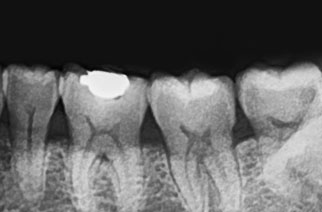

Oral Photography / Bite-Wing Radiography / Periapical Radiograph

[ 拍摄口腔内部 ]

从前牙到后牙, 临街牙齿部位,

牙齿平面的蛀牙及治疗状态都能扩大确认 . -

[ 拍摄咬翼 ]

为了更仔细确认牙齿头部拍摄X光片,

有效预防不能早期发现的牙齿面蛀牙 . -

[ 拍摄牙根 ]

* 需要时拍摄为了更仔细, 精密的检查问题牙齿拍摄X光片,

牙根底部炎症, 牙齿根管状态, 一般蛀牙等2次蛀牙都能确认 .